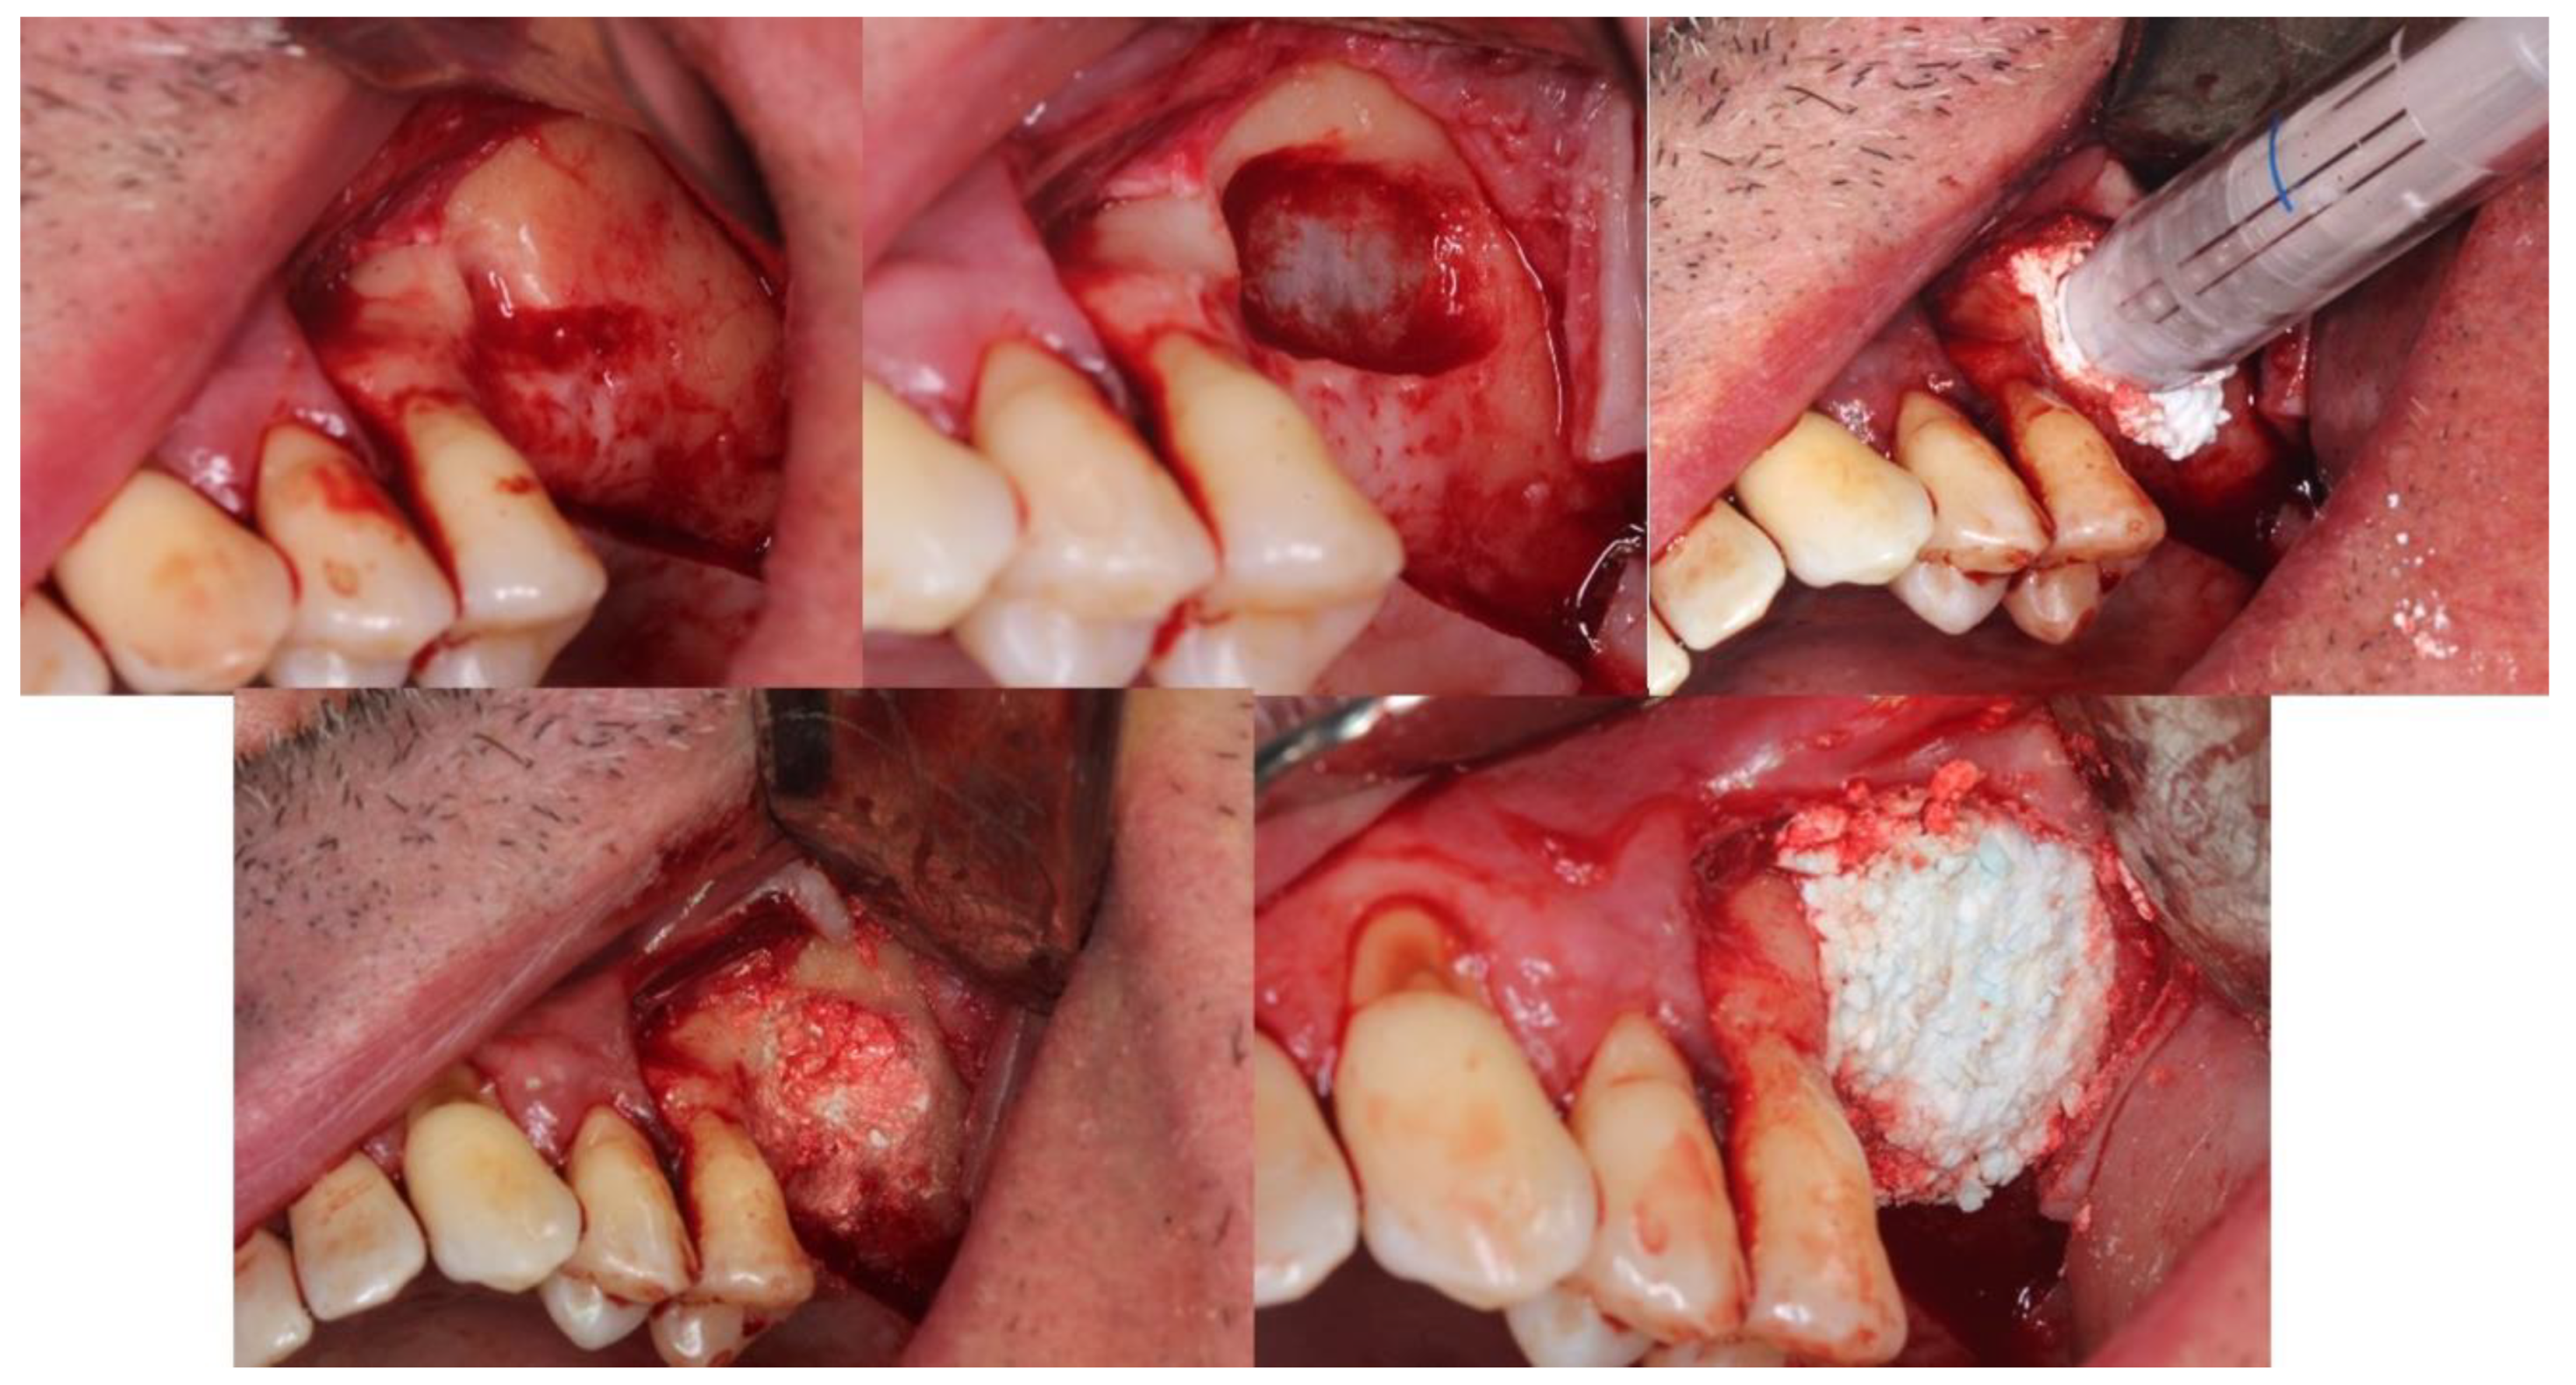

4.5. Patient No.5

4.6. Patient No.6